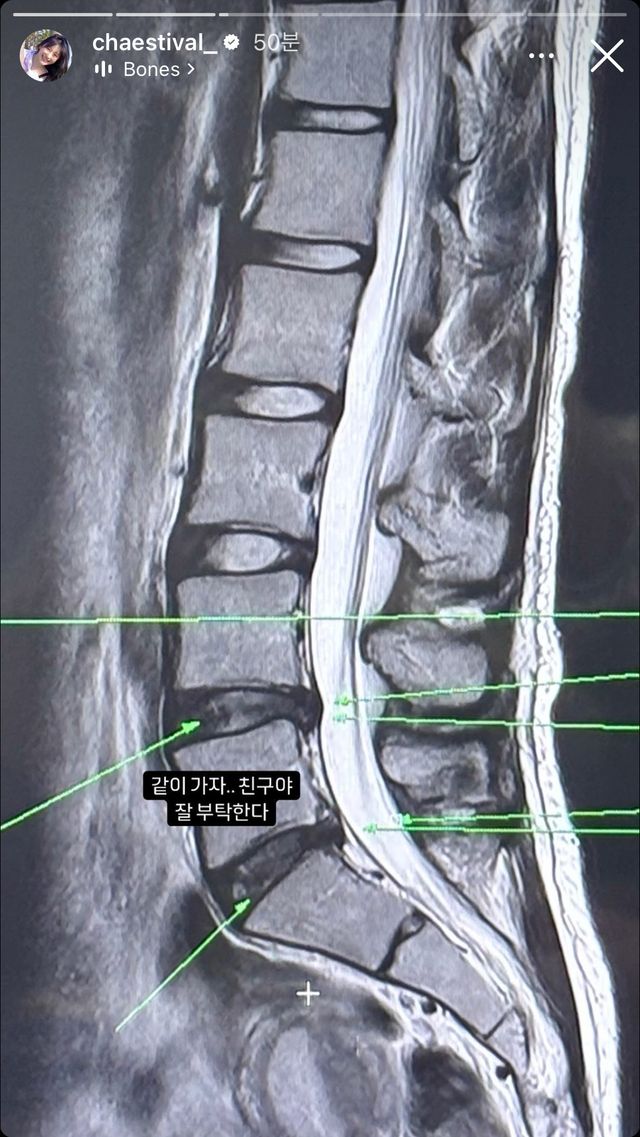

당분간 춤 못 춘다는 이채연 허리 상태

디스크 터짐